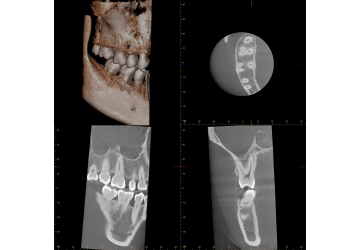

当院では3Dパノラマ撮影装置(ベラビューエポックス3Dfα)を導入しています。

立体的に詳細なお口の情報が把握でき、画像のクオリティも非常に高いので、

より正確な診断を可能にしています。

また、必要な箇所だけの撮影ができ、より少ないX線照射線量で撮影が可能ですので、

安心してご利用いただけます。